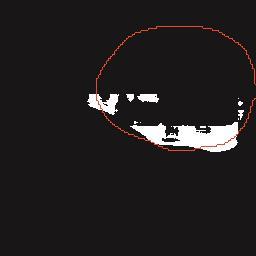

乳腺癌是全球女性最常见的恶性肿瘤之一,准确的病变分割对于乳腺癌的早期诊断与治疗具有重要意义。然而,由于病变形态的多样性以及超声成像机制的复杂性,现有基于深度学习的乳腺超声图像病变分割方法在分割准确性方面仍面临巨大挑战。为进一步提升乳腺超声图像中病变区域的分割精度,该文基于经典U-Net架构,提出了一种新型乳腺超声图像病变分割网络(CWSASKM-BBAM-Net)。首先,在网络中引入逐通道空间自适应选择核卷积模块(CWSASKM),根据不同通道的语义特征为每个空间位置自适应选择感受野大小,以增强多尺度信息的建模能力;然后,引入双向边界感知机制(BBAM),通过融合正向与反向注意力,对目标显著区域及其边界进行协同建模,同时逐步提升对非显著区域与病变区域的区分能力,以进一步强化边界信息的表达;最后,在3组公开乳腺超声图像数据集(BUSI、UDIAT和STU)上开展分割实验。结果表明:该方法在数据集BUSI上的杰卡德指数、精确率、召回率和Dice相似系数分别为71.97%、82.85%、81.40%和80.44%,较次优方法分别提升1.69、1.05、1.28和1.84个百分点;在数据集UDIAT上,这4项指标分别达到78.14%、88.31%、86.73%和86.10%,较次优方法分别提升了2.75、2.04、0.56和2.01个百分点;在外部数据集STU上,该方法也取得了优于其他方法的整体表现。实验结果表明,CWSASKM-BBAM-Net在乳腺超声图像分割任务中展现出更优的整体性能。